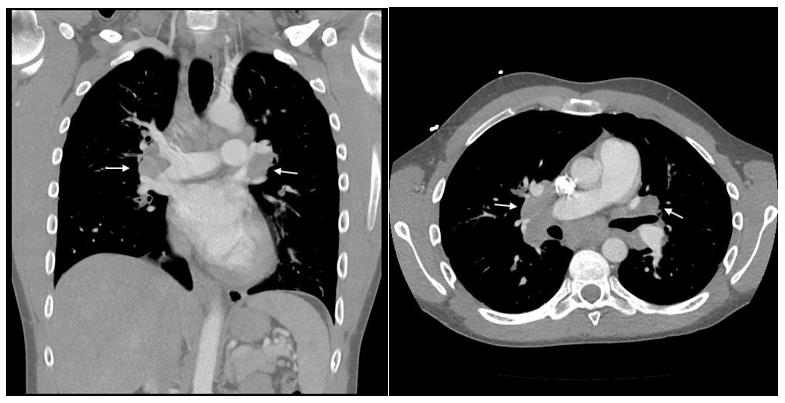

He was admitted to an outside hospital for severe right ankle swelling and underwent incision and drainage of his right posterior tendon tibial sheath for suspected septic arthritis. The aspirarate was clear, non-purulent and without growth on culture. Laboratory investigations were significant for WBC of 5.08 (ref 4.31-6.4 uL), normal absolute eosinophils, angiotensin converting enzyme (ACE) of 44 U/L (ref 9-67 U/L), negative chlamydia and gonorrhea PCR, and negative ANA and ANCA titers. He also had a negative quantiferon gold test four months prior to presentation. A chest CT demonstrated extensive, bilateral hilar and mediastinal adenopathy (Figure 1). He was started on vancomycin and discharged with cephalexin for right ankle cellulitis. His symptoms transiently improved on antibiotics but he was rehospitalized for progressive arthralgia, fevers, and new onset tender nodules on the left forearm four days later. On readmission, he was febrile to 38.1 C with otherwise normal vital signs.

The differential diagnosis included infection, eGPA nodules, and Löfgren syndrome. Cultures and quantiferon were negative making infectious panniculitis less likely. EGPA nodules were considered, however this patient’s ankle arthritis, erythema nodosum, and hilar lymphadenopathy were most consistent with Löfgren syndrome. He was started on a dexamethasone 16-day taper starting at 6 mg daily and mepolizumab was continued. Post-discharge follow-up with rheumatology demonstrated resolution of arthritis, erythema nodosum, along with normalization of inflammatory markers. Three months post-treatment, his chest x-ray demonstrated decreased appearance of mediastinal and hilar lymphadenopathy when compared to prior CT (Figure 3). One year later, the patient continues to take mepolizumab without corticosteroids, and has had no recurrence of his symptoms.